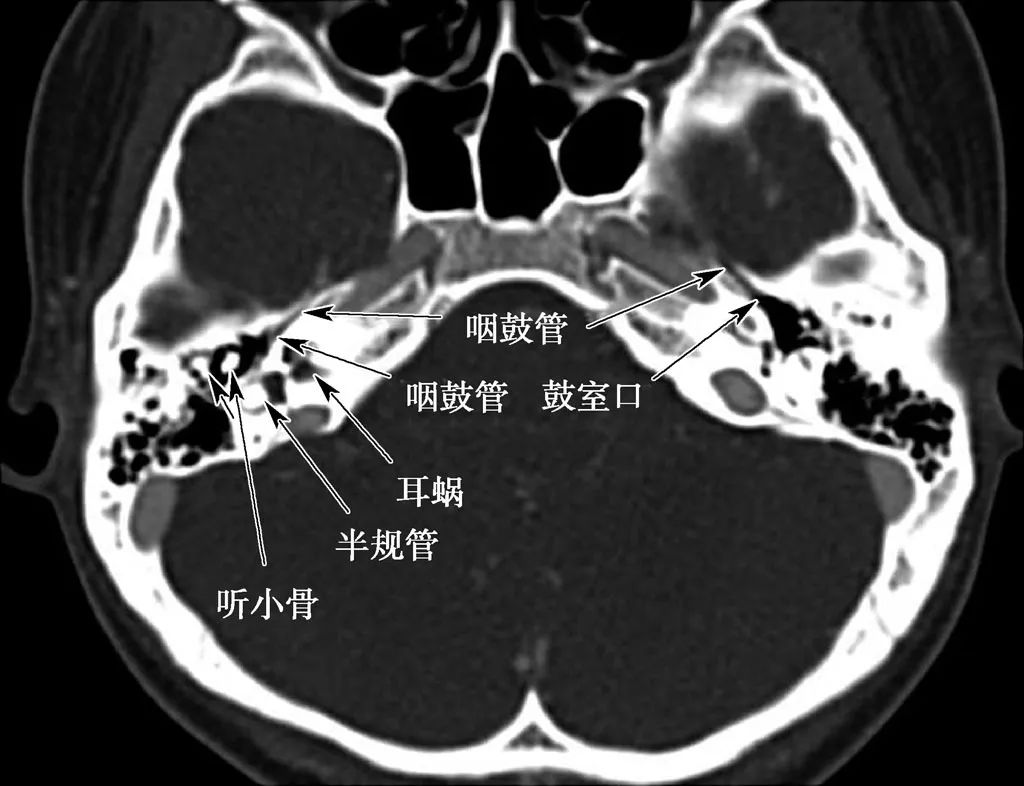

中耳、内耳结构

(CT横断面自上而下)

咽鼓管结构

A. CT;B. MRI